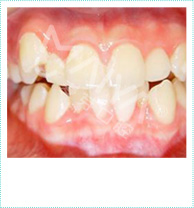

重塑正确咬合关系

解决各类牙齿畸形

提升咀嚼效能

预防蛀牙牙病